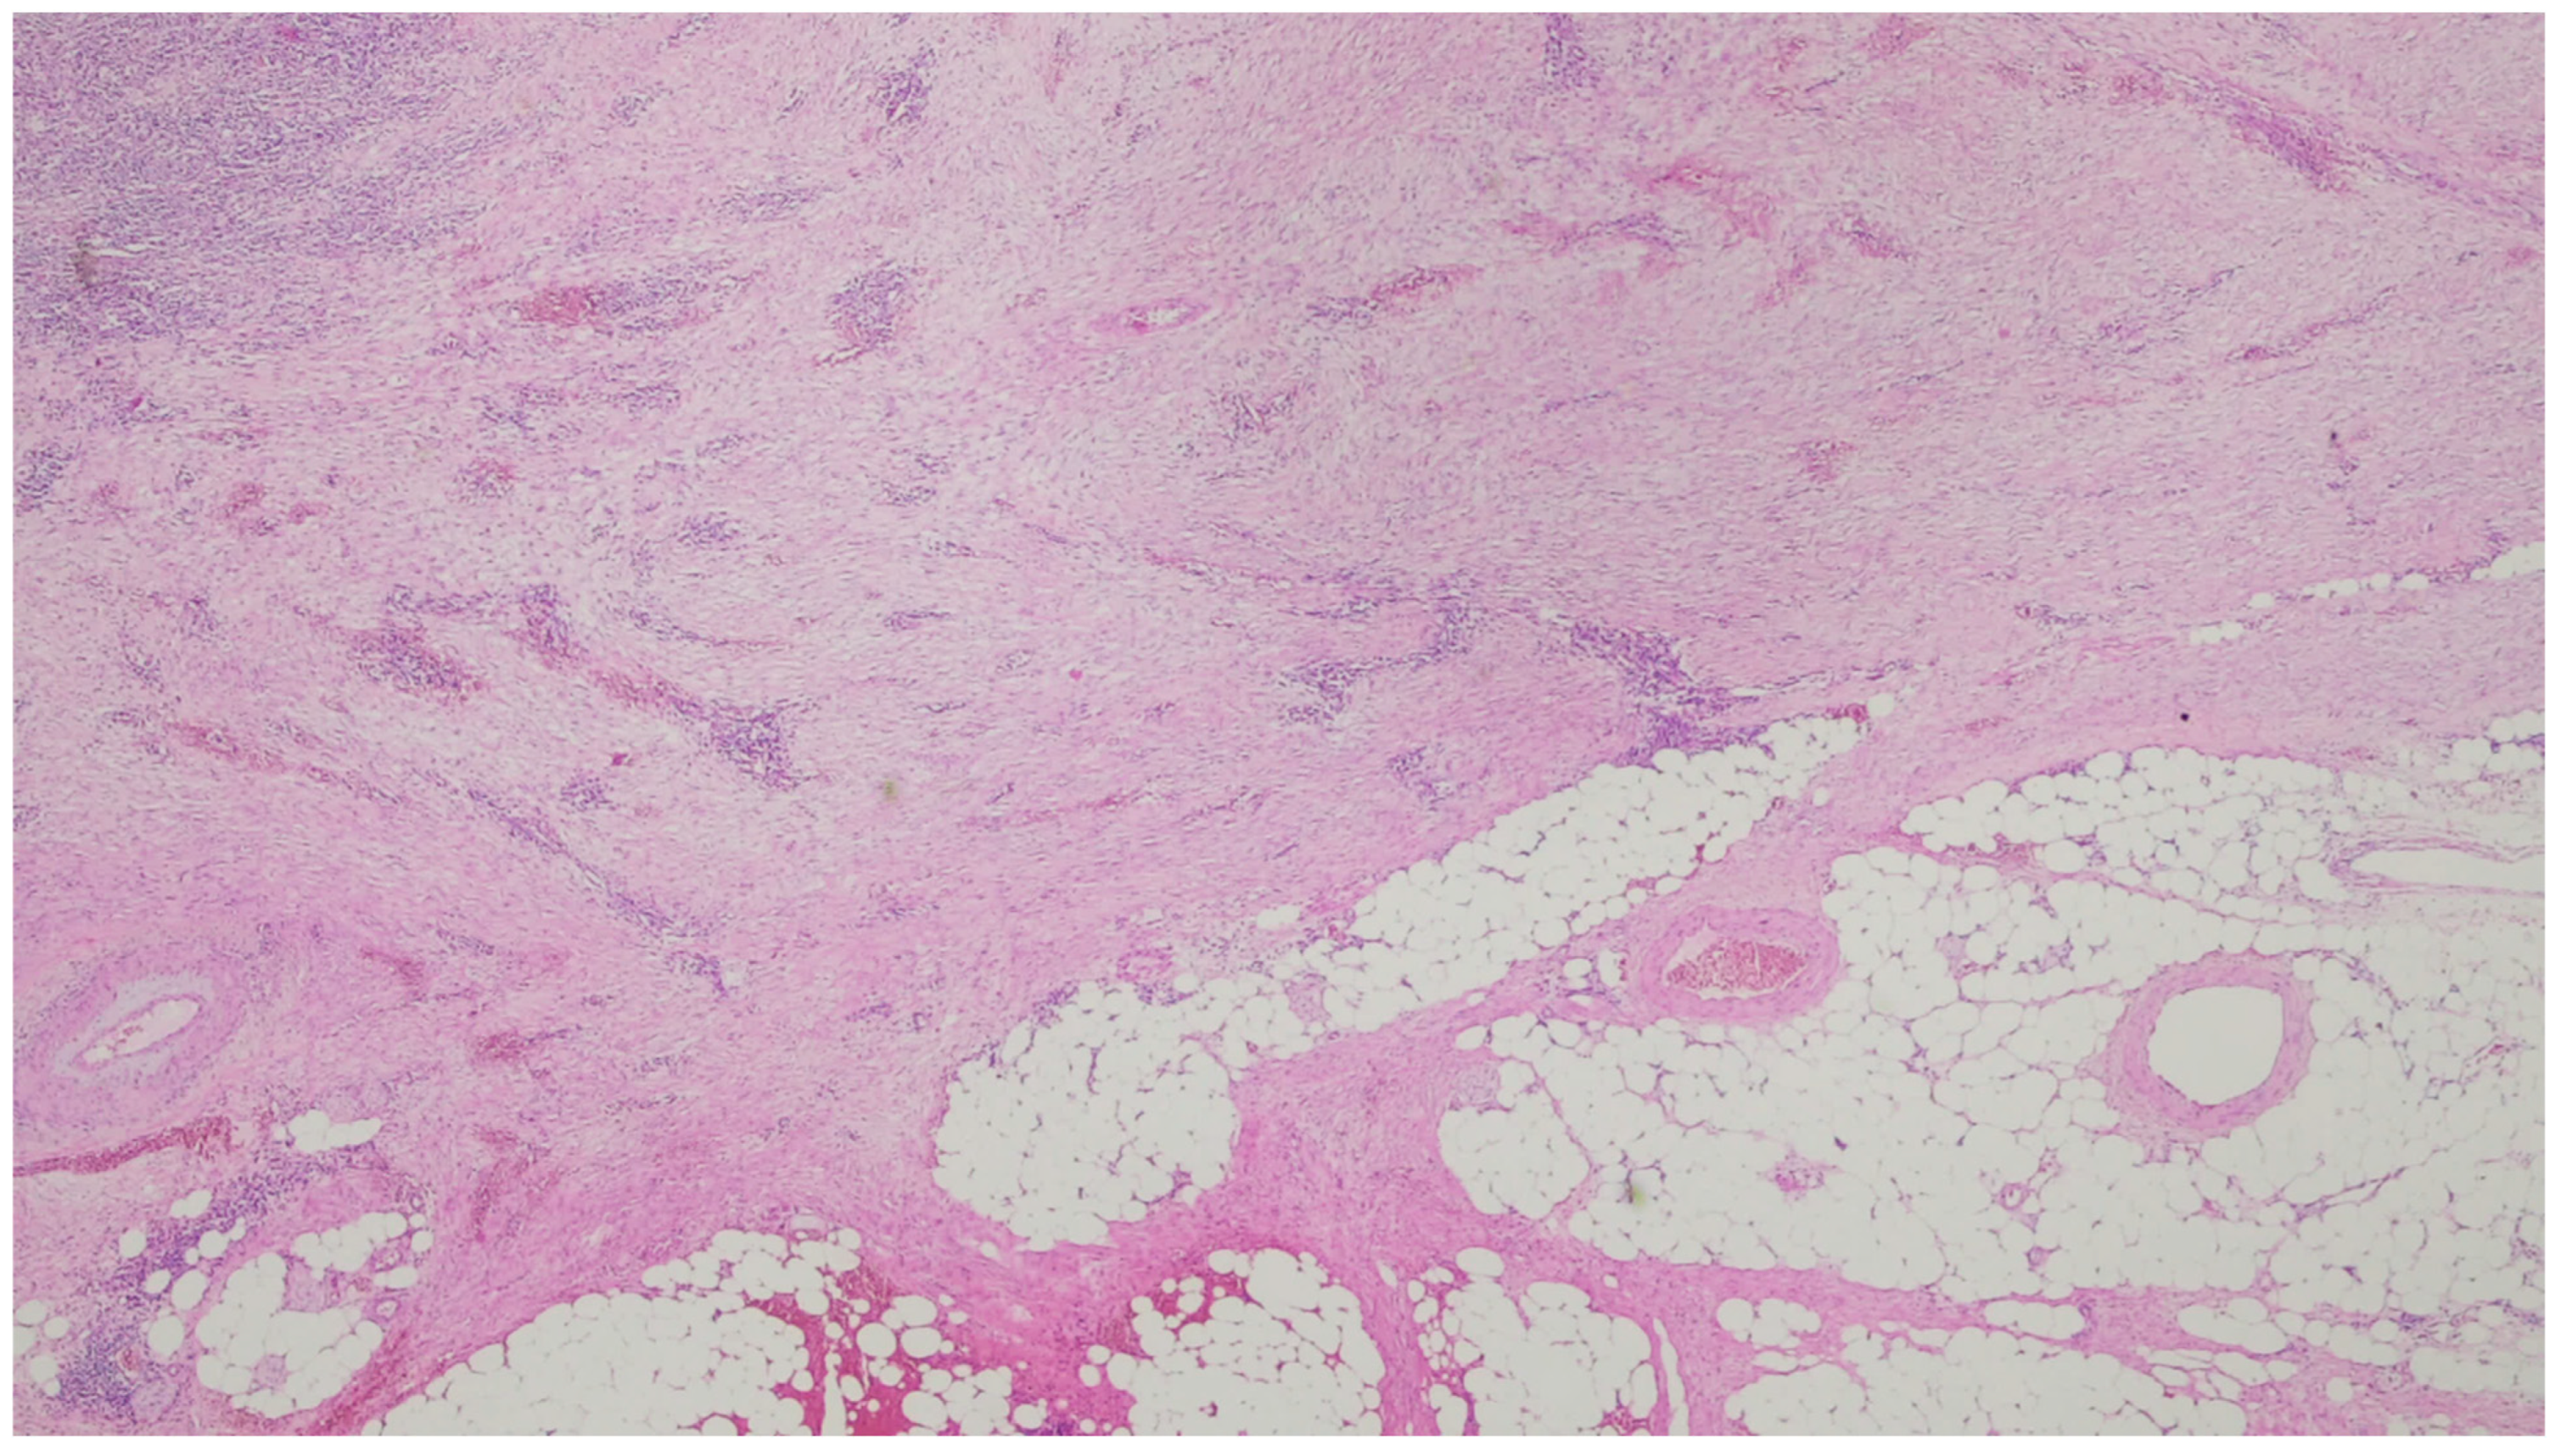

| Fibromatosis | 30 and 40 years | Mesentery of the small bowel | Abdominal pain | Long fascicles of spindle cells with ovoid nuclei without atypia or necrosis | Β-catenin |